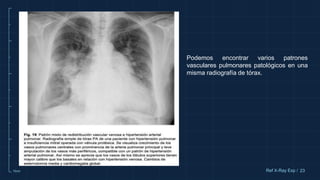

Podemos encontrar varios patrones

vasculares pulmonares patológicos en una

misma radiografía de tórax.